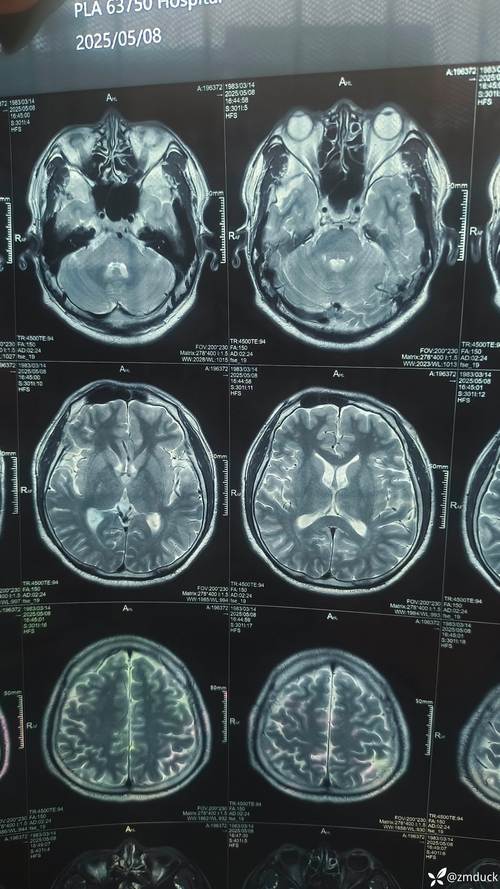

- 影像学检查:

- 头部CT或MRI:排除颅内病变、血管炎或狼疮脑病。